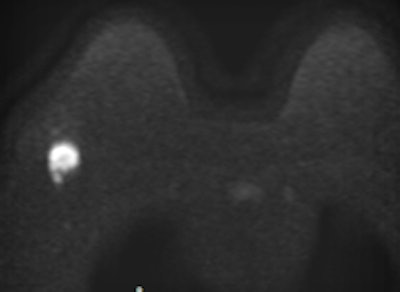

Invasive ductal carcinoma with positive axillary lymphadenopathy. The detection of malignant masses is relatively easy using DWI for both index tumor and axillary positive lymph node. ADC values of the index tumor and positive homolateral lymph node were less than 0.9. This case illustrates the usefulness of DWI to detect both index tumor and positive lymphadenopathy. Images courtesy of Dr. Isabelle Thomassin-Naggara.